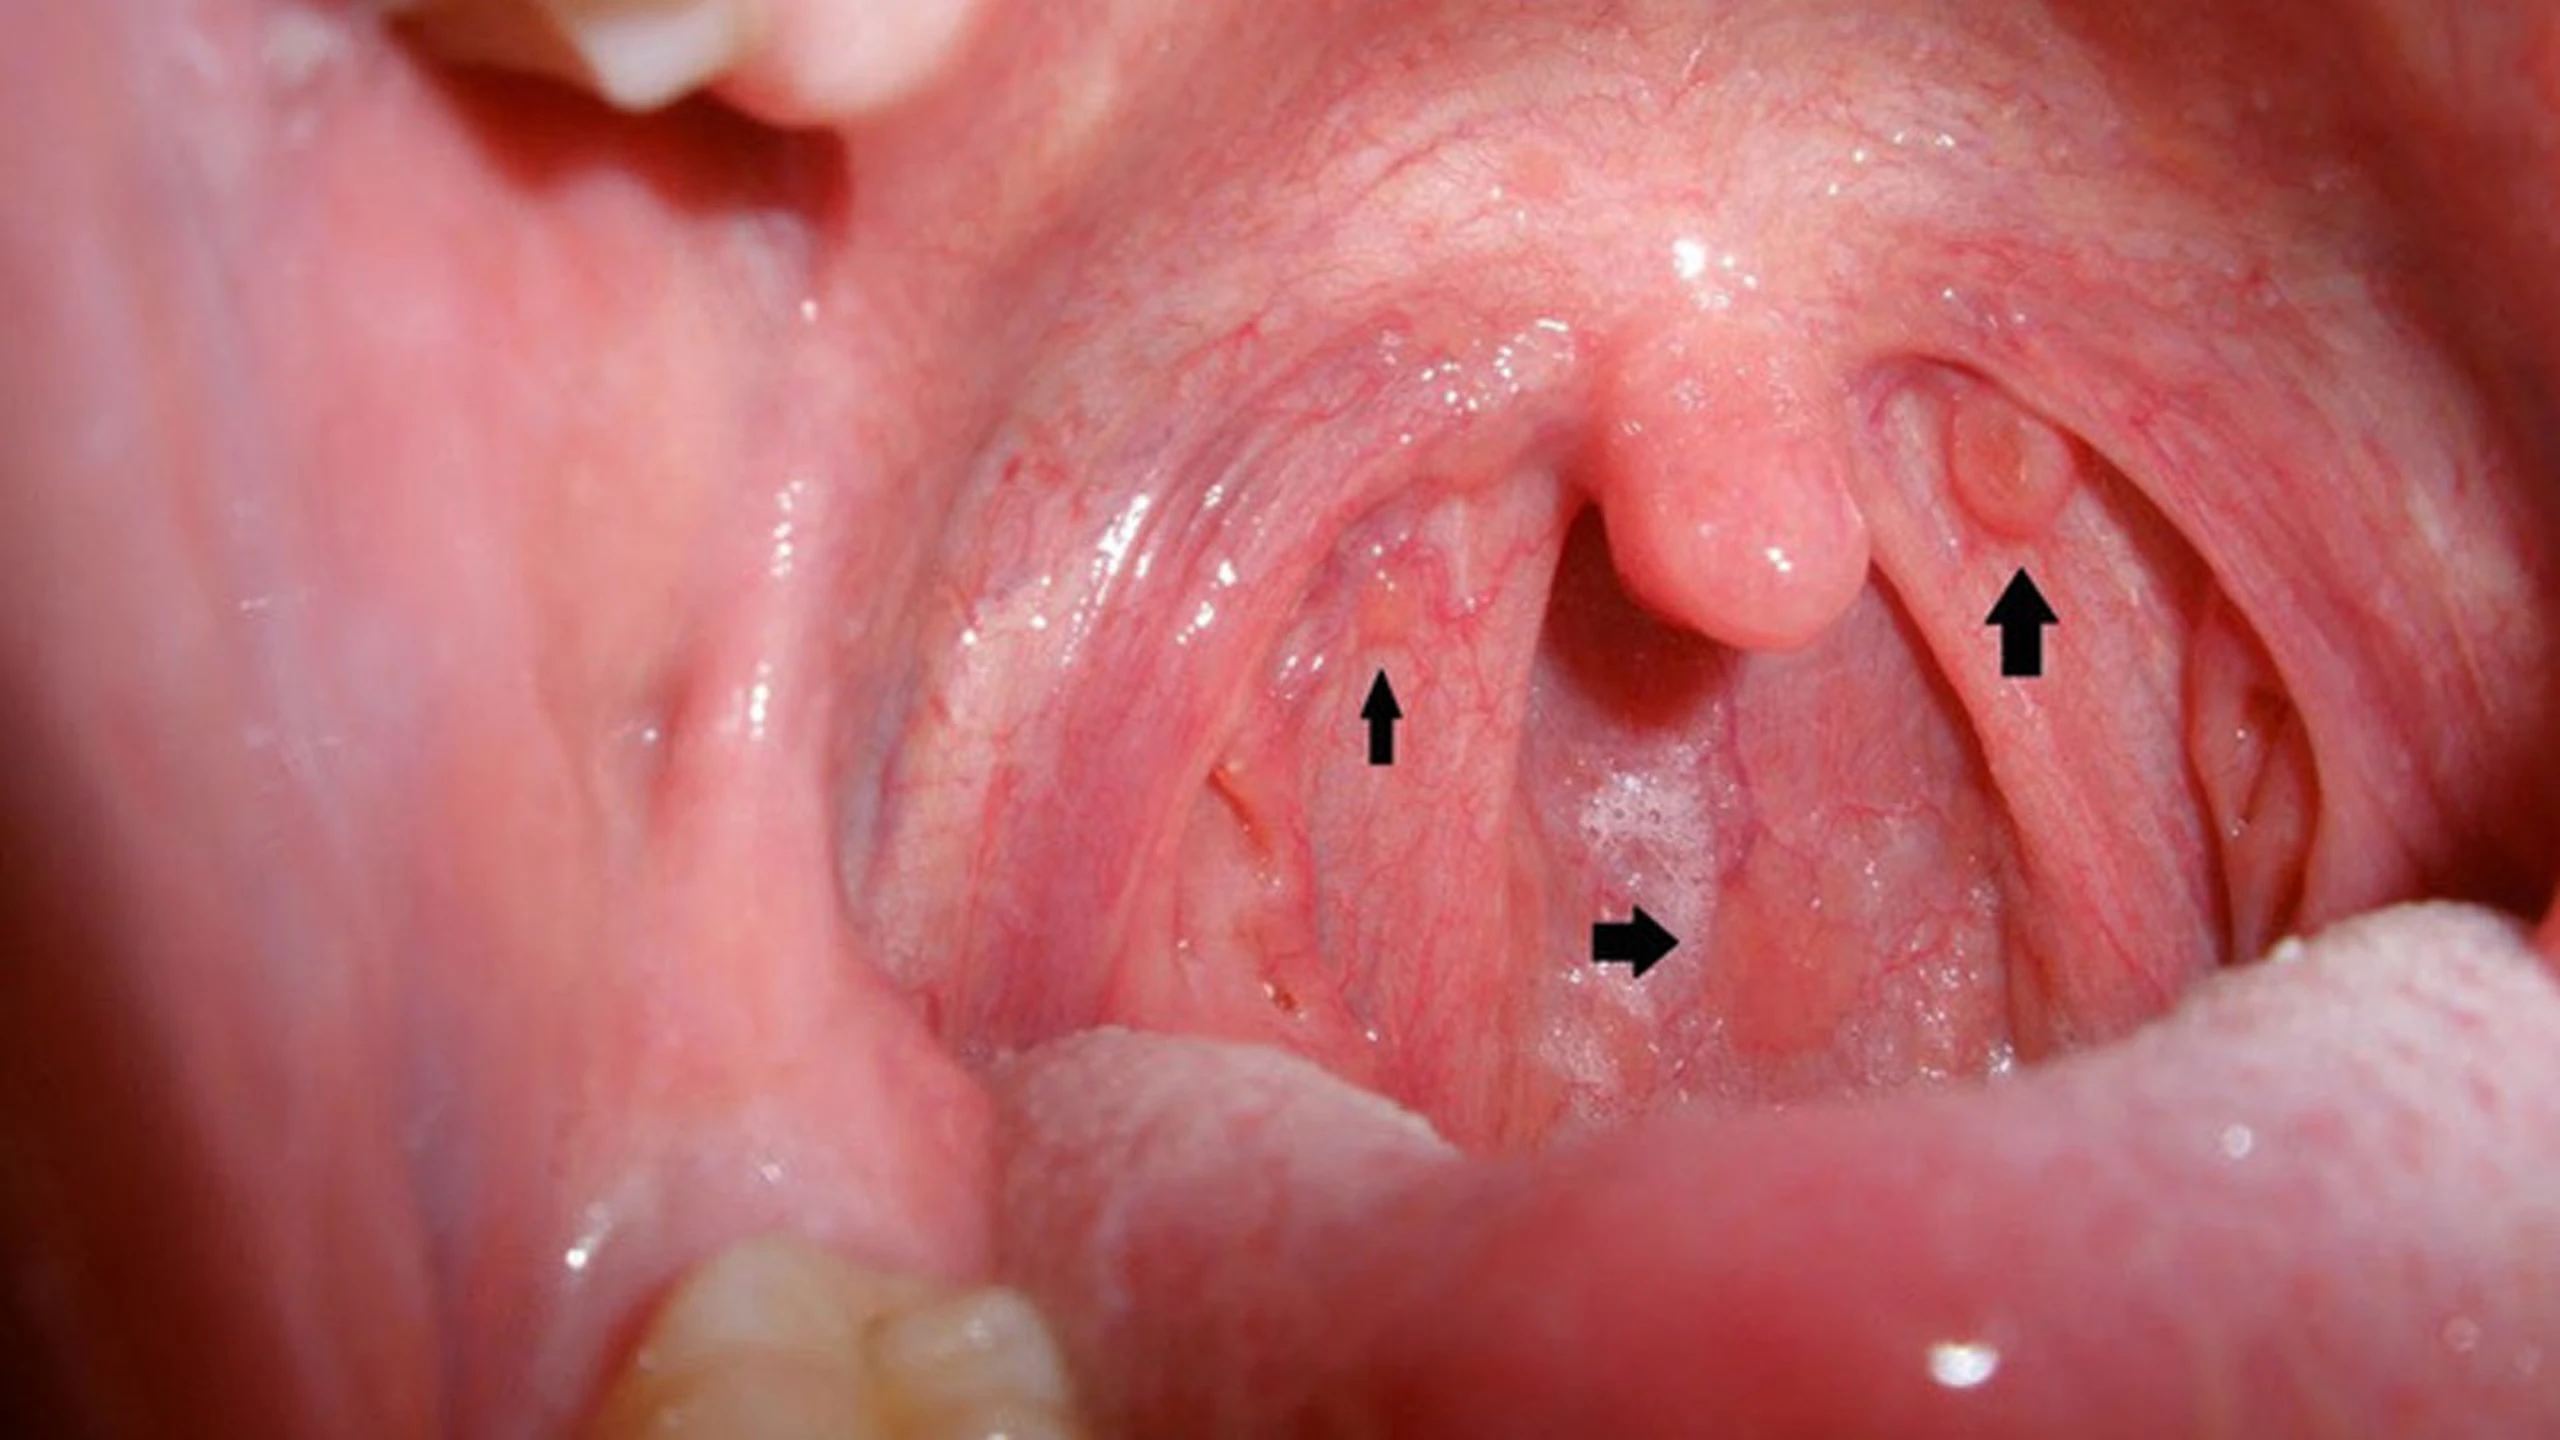

Viêm họng hạt mãn tính là một dạng phổ biến của bệnh viêm họng mãn tính, đặc trưng bởi tình trạng viêm kéo dài liên tục. Tình trạng này khiến niêm mạc họng của bạn bị sung huyết và tiết dịch liên tục, tạo ra cảm giác khó chịu. Khi niêm mạc bị viêm, cơ thể sẽ trở nên yếu ớt hơn, khiến cho hệ miễn dịch dễ bị tấn công bởi các tác nhân gây bệnh như virus hoặc vi khuẩn. Kết quả là sự hình thành các hạt màu đỏ hoặc hồng ở phía sau họng, gây ra nhiều triệu chứng khó chịu.

Các hạt xuất hiện ở niêm mạc họng thường là kết quả của việc nhiễm trùng kéo dài, khiến các nang lympho - có vai trò quan trọng trong việc bảo vệ cơ thể và hệ hô hấp khỏi virus và vi khuẩn - phải hoạt động quá mức. Khi các nang lympho này liên tục bị kích thích và hoạt động mạnh mẽ, chúng có thể tăng sản, dẫn đến hình thành các hạt nổi cộm trên niêm mạc họng. Chính vì vậy, viêm họng hạt mãn tính thường gặp ở những bệnh nhân có tiền sử viêm họng dai dẳng hoặc tái phát nhiều lần.